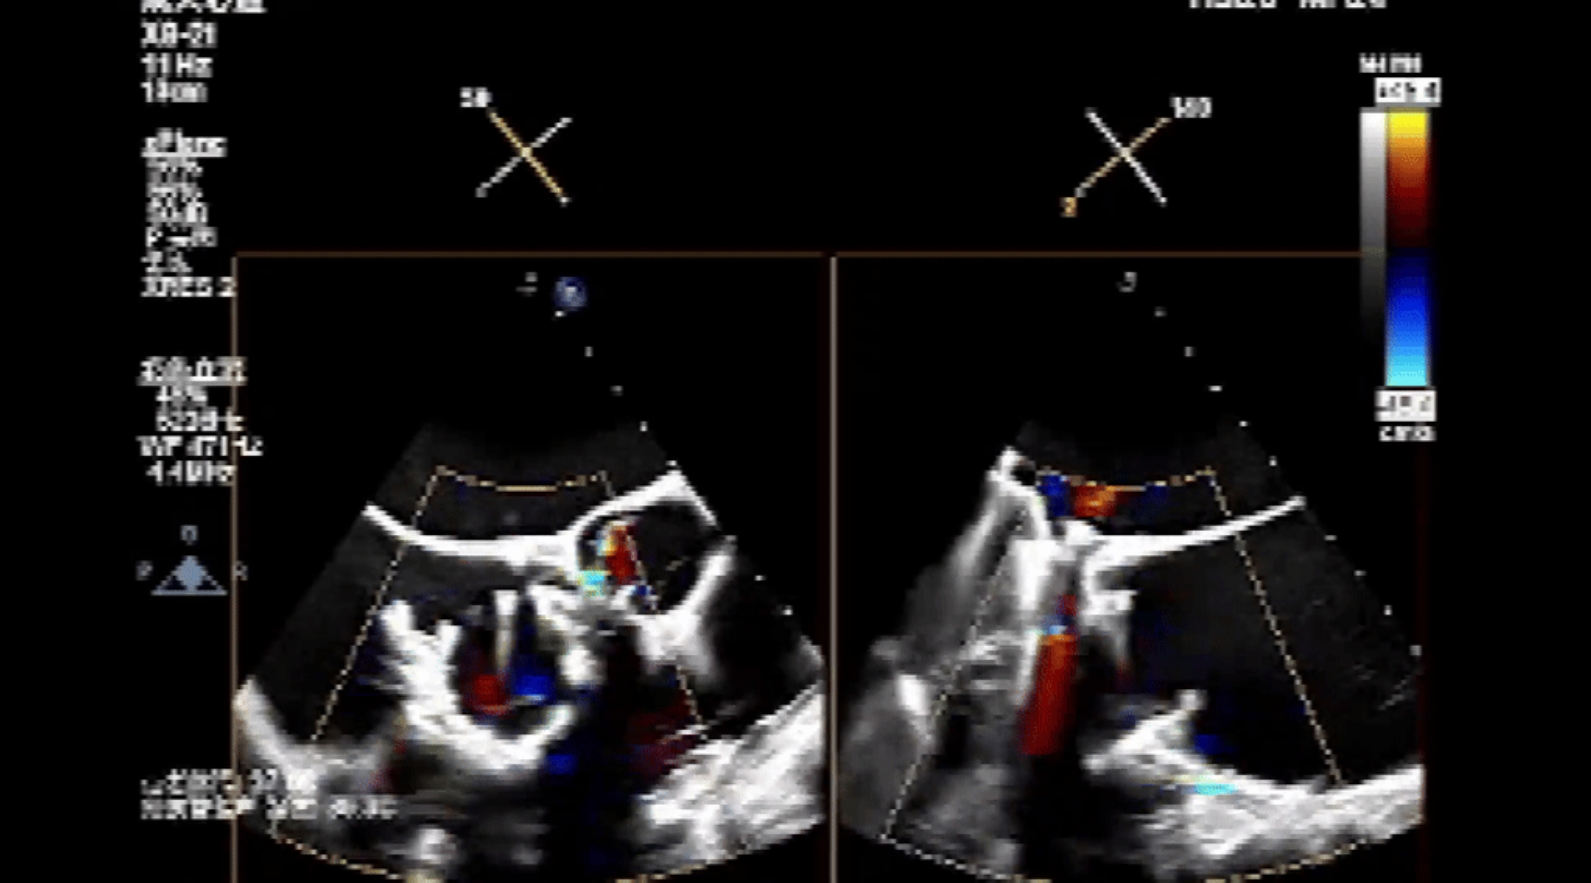

術(shù)前心臟超聲提示:三尖瓣大量返流,右心房容積明顯增大,三尖瓣瓣環(huán)顯著擴張。

術(shù)后心臟超聲提示:Lux-Valve Plus植入術(shù)后,三尖瓣瓣環(huán)處可見人工瓣膜回聲,未見返流,人工瓣膜穩(wěn)定,瓣葉開閉良好,連續(xù)多普勒估測三尖瓣平均跨瓣壓差僅為1mmHg。